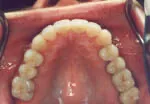

Composite resins, inlays and onlays are tooth-colored restorations that are used in place of silver fillings on the chewing surfaces of back teeth. Unlike silver fillings made from metals that may cause further damage to teeth, these cosmetic fillings look extremely natural and typically require that far less of the tooth be removed.